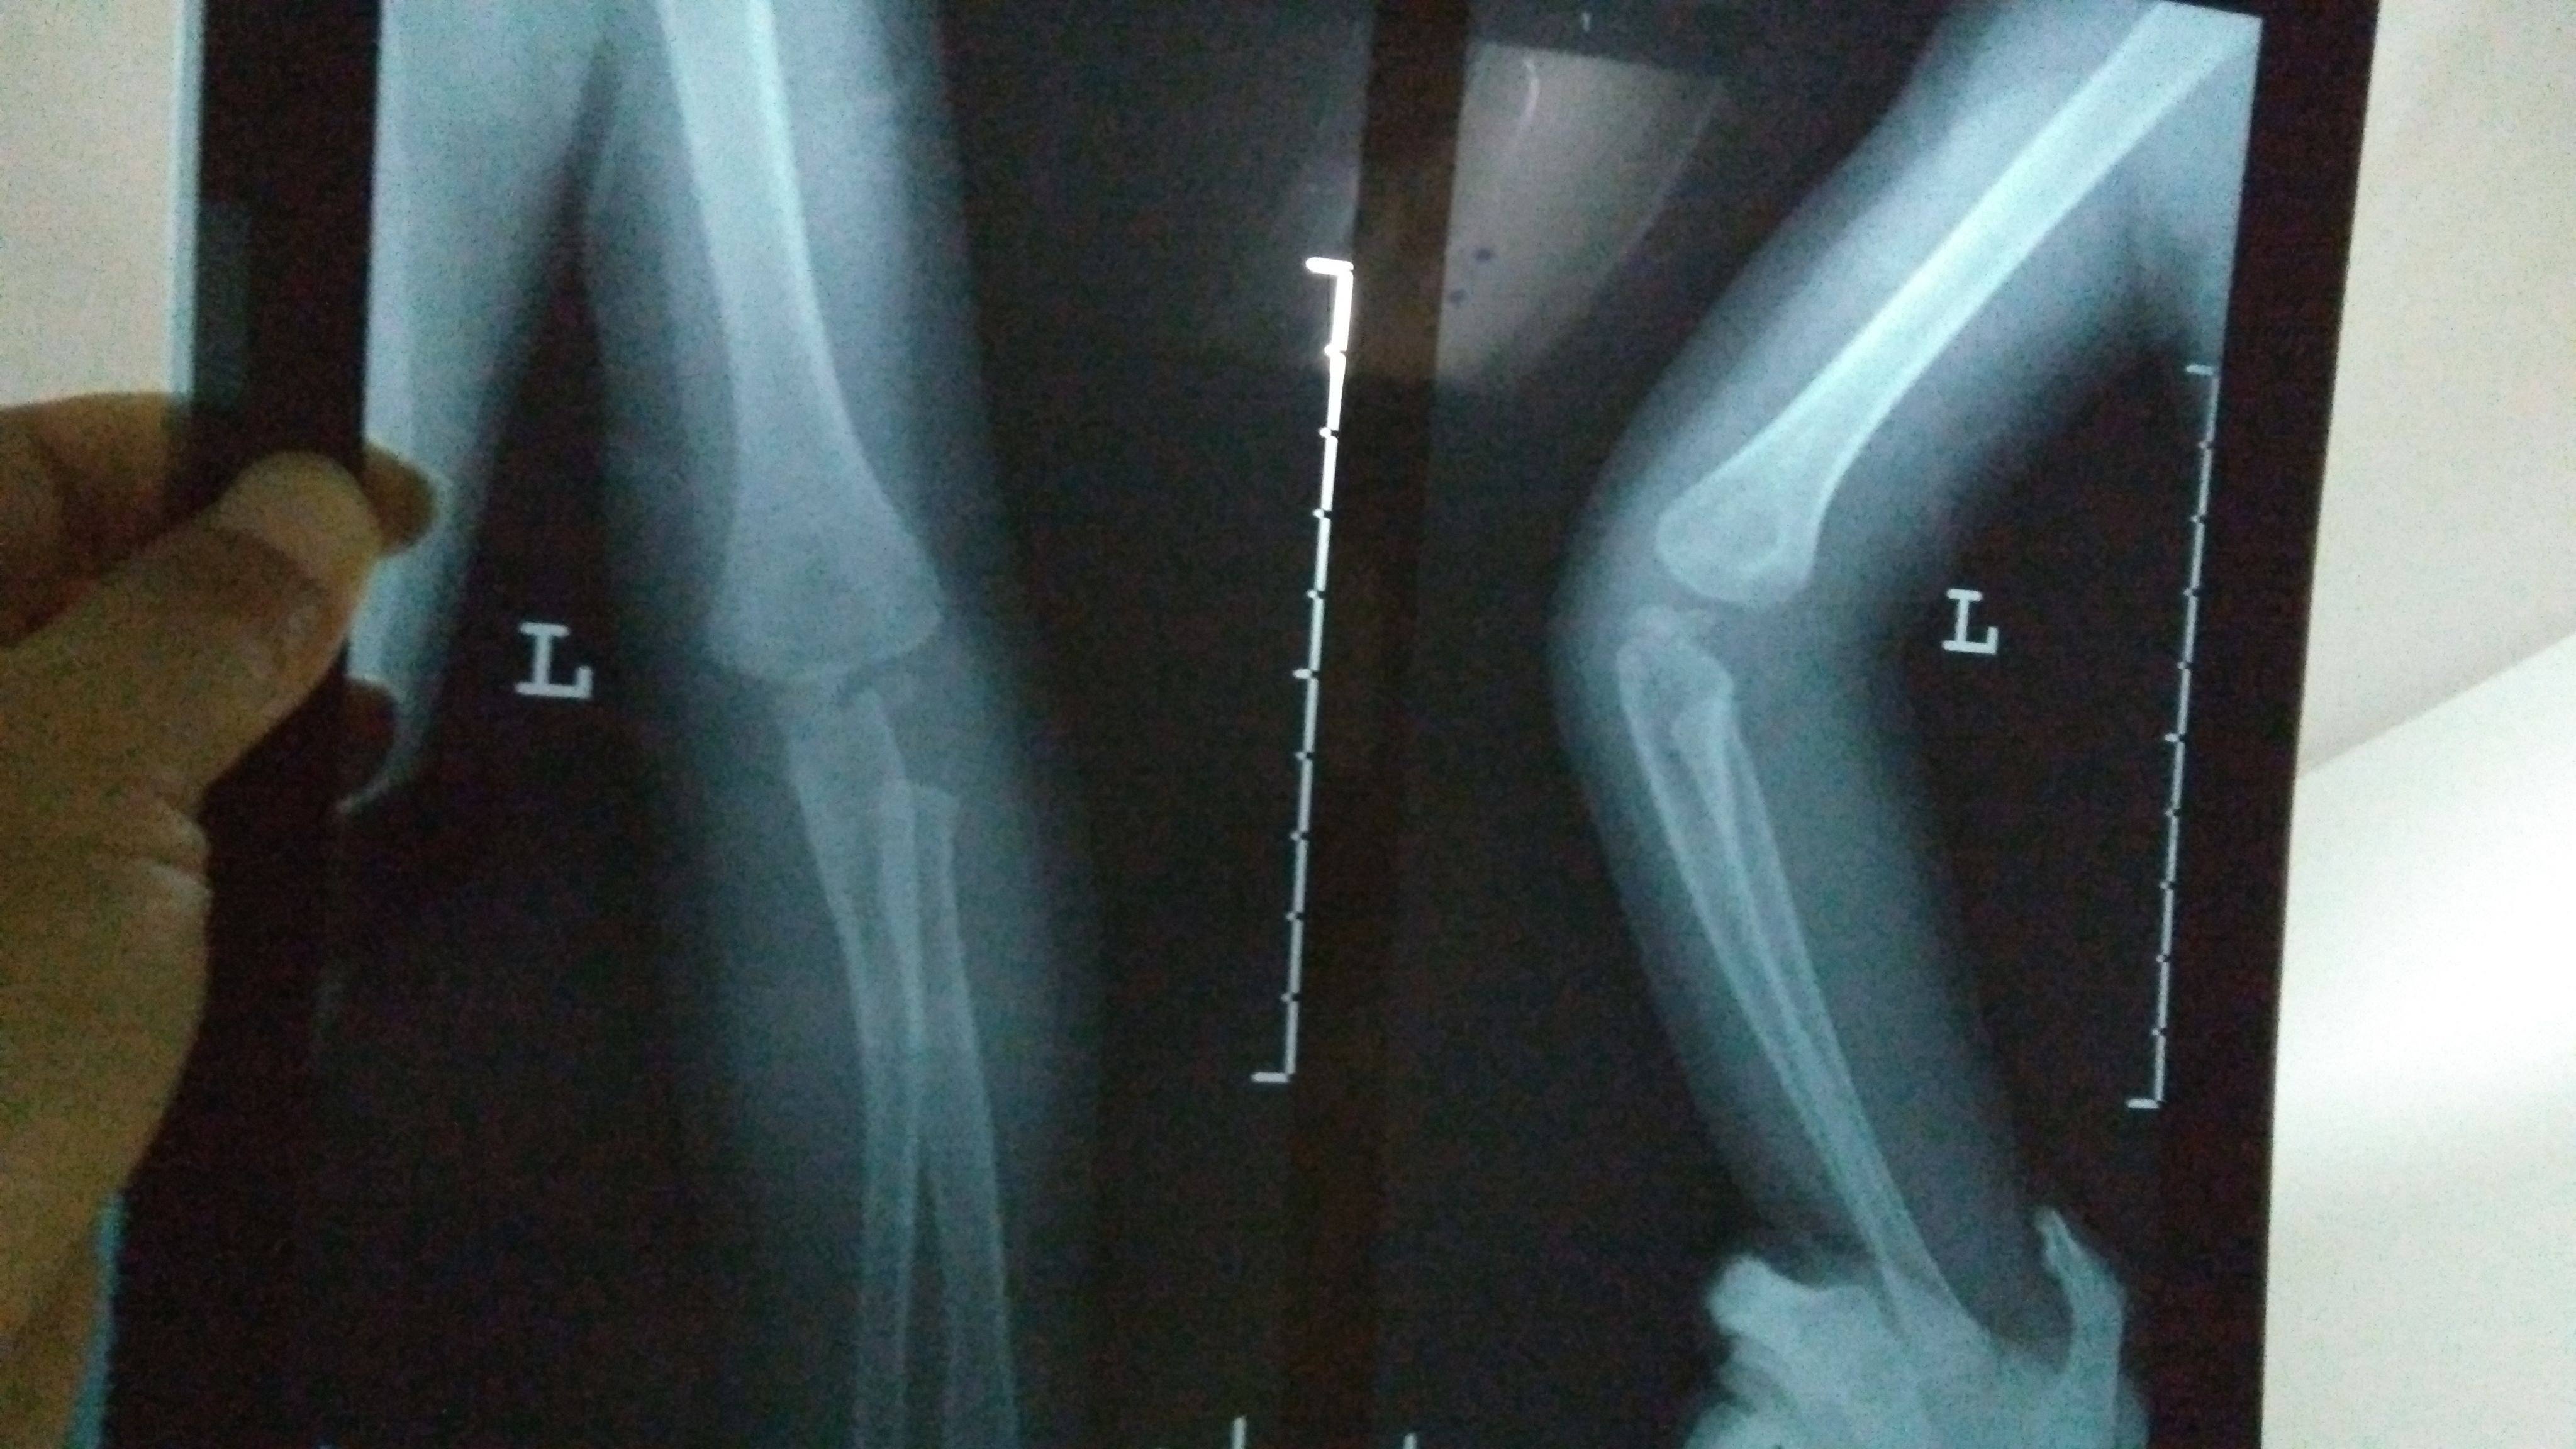

2岁宝宝骨折,急急急! 宝宝今晚玩耍奔跑时,摔倒姿势有异(速度很快不小心扑倒了,整个左手臂压在他自己身下,当时就骨折了)。 宝宝一直出冷汗表情痛苦哭,左手不动弹,我们赶紧去医院。以下是X光片(左手)和报告,打了石膏,医生让4-7天内去复查。 另外医生说小儿骨折这个部位骨垢骨折的情况比较少见,需要我明天带着片子报告去给他们主任看一下,看是否会影响手臂的功能性。如果有功能性影响,会影响孩子发育,还得纠正,做手术。 我知道医生总是会预先把最坏的结果告知患者,可是伤在儿身,痛在娘心。我担心害怕要做手术,加上回家后老公一直在说医生当时石膏没打好,让我带宝宝明天去重新打过石膏…说医生不太靠谱。确实,那个医生打石膏的时候还在接电话,一直不停跟他家人打电话接电话。 恳求有懂小儿骨折的医生帮帮我,看看我宝宝这个情况到底怎样?会影响他发育吗?可能要做手术纠正吗?跪求了!万分感谢!

这个部位骨折是非常清楚的,先打石膏固定一下(不可重复打石膏),看看恢复情况,如果效果不好一周之内要手术治疗!